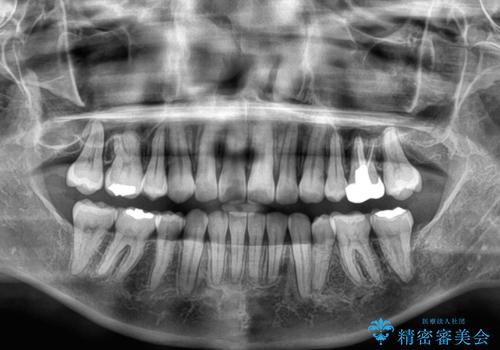

上下左右の第一小臼歯4本を抜歯して治療を行うことがセオリーでしたが、左下は第二小臼歯が銀歯であったため、イレギュラーではありますが、そちらを抜歯しました。

その影響で治療期間は長くなりましたが、処置していない歯を保存することができました。